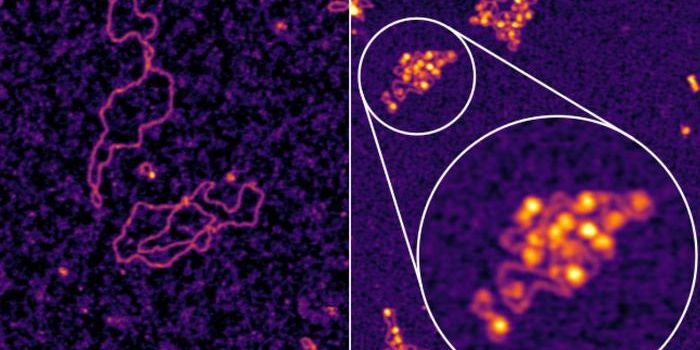

MAR 21, 2025Drug Discovery & DevelopmentIn the rapidly evolving field of drug discovery, single-cell analysis has become an invaluable tool for understanding ce ...